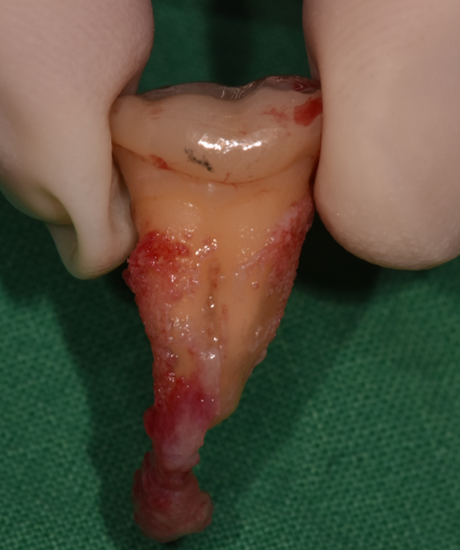

치료 전

의도적 발치 직후 뿌리 끝 염증 관찰